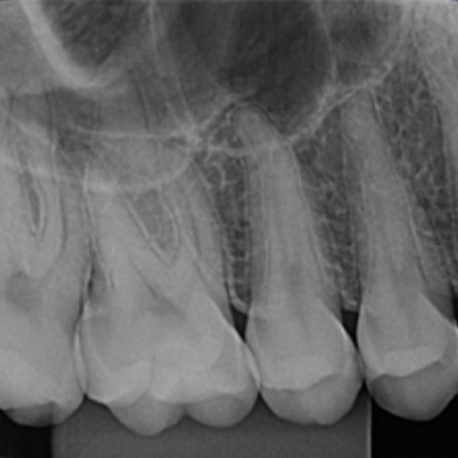

A radiografia periapical é o exame mais frequente no que diz respeito às radiografia intra orais. Esse exame serve para visualizar radiograficamente a anatomia de um ou mais dentes (desde a coroa até ao término da raiz), assim como as estruturas anatómicas vizinhas, que estão ao redor dos dentes. Esta radiografia pode ser usada para estudar qualquer um dos dentes (molares, pré-molares, incisivos e caninos), seja na arcada dentária superior ou na inferior. Permitindo avaliar a anatomia do dente e da região ao redor de forma mais detalhada.